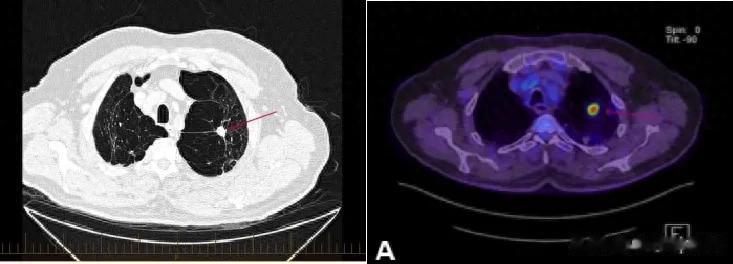

这位大爷来自澳大利亚,2020年时因为计划进行颈椎手术做了次颈部CT检查,却意外发现左肺上叶有一处17mm的毛刺状肺结节,经活检和PET/CT确认为IIB期的非鳞癌,而且PD-L1肿瘤比例评分(TPS)高达65%。

2020年确诊肺癌时的CT和PET/CT影像